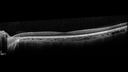

25 year old with AD optic atrophy. VA 20/80 OU. Her father also had vision loss and optic atrophy.

Autosomal Dominant Optic Atrophy - OPA1 Mutation145 views25 year old female with VA 20/80 OU and recent vision decline. Her father also has poor vision.00000

Autosomal Dominant Optic Atrophy - OPA1 Mutation163 views25 year old female with VA 20/80 OU and recent vision decline. Her father also has poor vision.00000

Autosomal Dominant Optic Atrophy - OPA1 Mutation161 views25 year old female with VA 20/80 OU and recent vision decline. Her father also has poor vision.00000